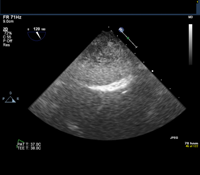

Given this history, the patient is scheduled for an elective transesophageal echocardiogram the day after presenting to the clinic. The images below show the TEE findings: a large 5.5-cm x 2.7-cm heterogeneous multilobulated mass, attached along the posterior wall of the left atrium, which likely represents a thrombus. (Click to enlarge the images.)